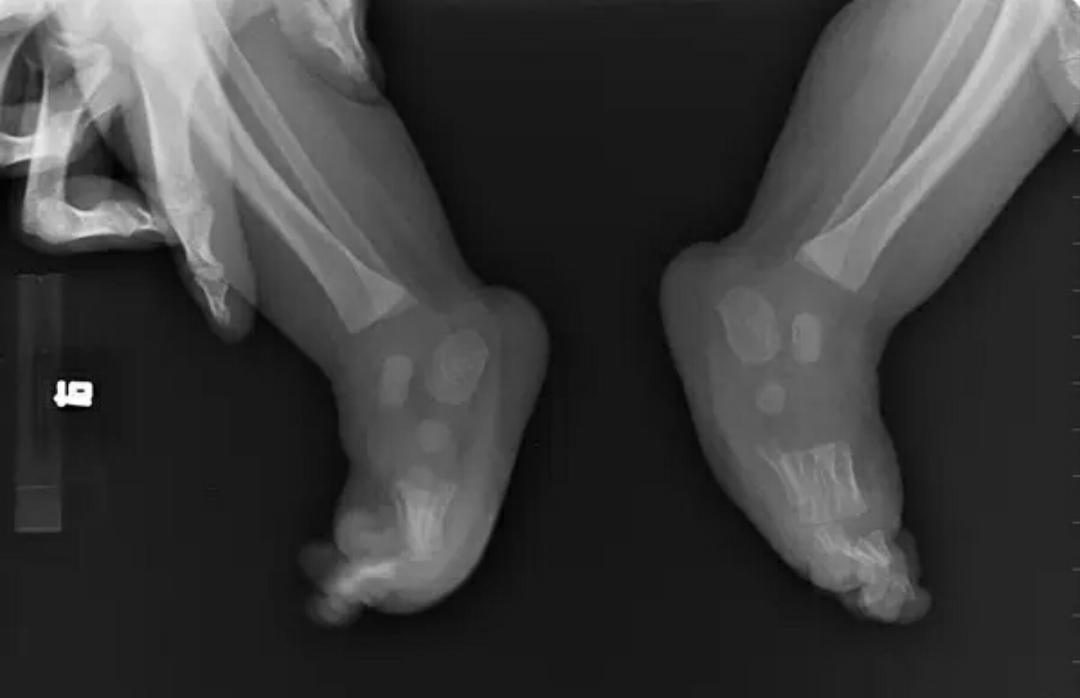

2.先天性马蹄足需要拍片吗?

答:先天性马蹄足因出生后就会发现,然而婴幼儿时期足部骨骼发育不完善,x线片往往显示欠佳,没有明显临床意义,所以一般不建议拍片检查。如果患儿较大就诊,超过1.5岁以上,拍片有一定的参考意义。下图是2个月小孩马蹄足的x线片:可见意义有限.